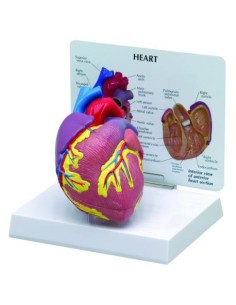

Des modèles anatomiques détaillés pour tous les besoins

Du crâne en 22 parties à verrouillage magnétique aux modèles de colonne vertébrale, des modèles d'articulation aux modèles de cœur, chaque pièce de notre collection est conçue pour une immersion totale dans l'étude de l'anatomie humaine. Nos modèles, réalisés à partir de scans d'os réels, garantissent une expérience tactile authentique et une fidélité de poids presque identique aux originaux.

Indispensables aux étudiants comme aux professionnels, nos modèles anatomiques sont des outils pédagogiques qui permettent d'observer les structures anatomiques avec précision, en évitant les dissections ou les études invasives. Ils sont également utiles pour expliquer les pathologies aux patients, ce qui rend la communication plus efficace et permet de gagner un temps précieux.